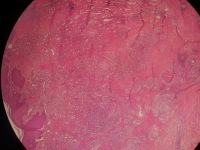

急!请老师帮忙看看,这个报告怎么发

性别

男

年龄

52岁

临床诊断

头皮肿物

一般病史

发现头皮肿物4~5年,平时经常触摸及抓挠

标本名称

头皮肿物切除术

大体所见

带皮组织0.9x0.6x0.2厘米~2.0x1.0x0.6厘米3块,未见明显肿物,送检组织呈片状,上带毛发。

肉芽组织型血管瘤